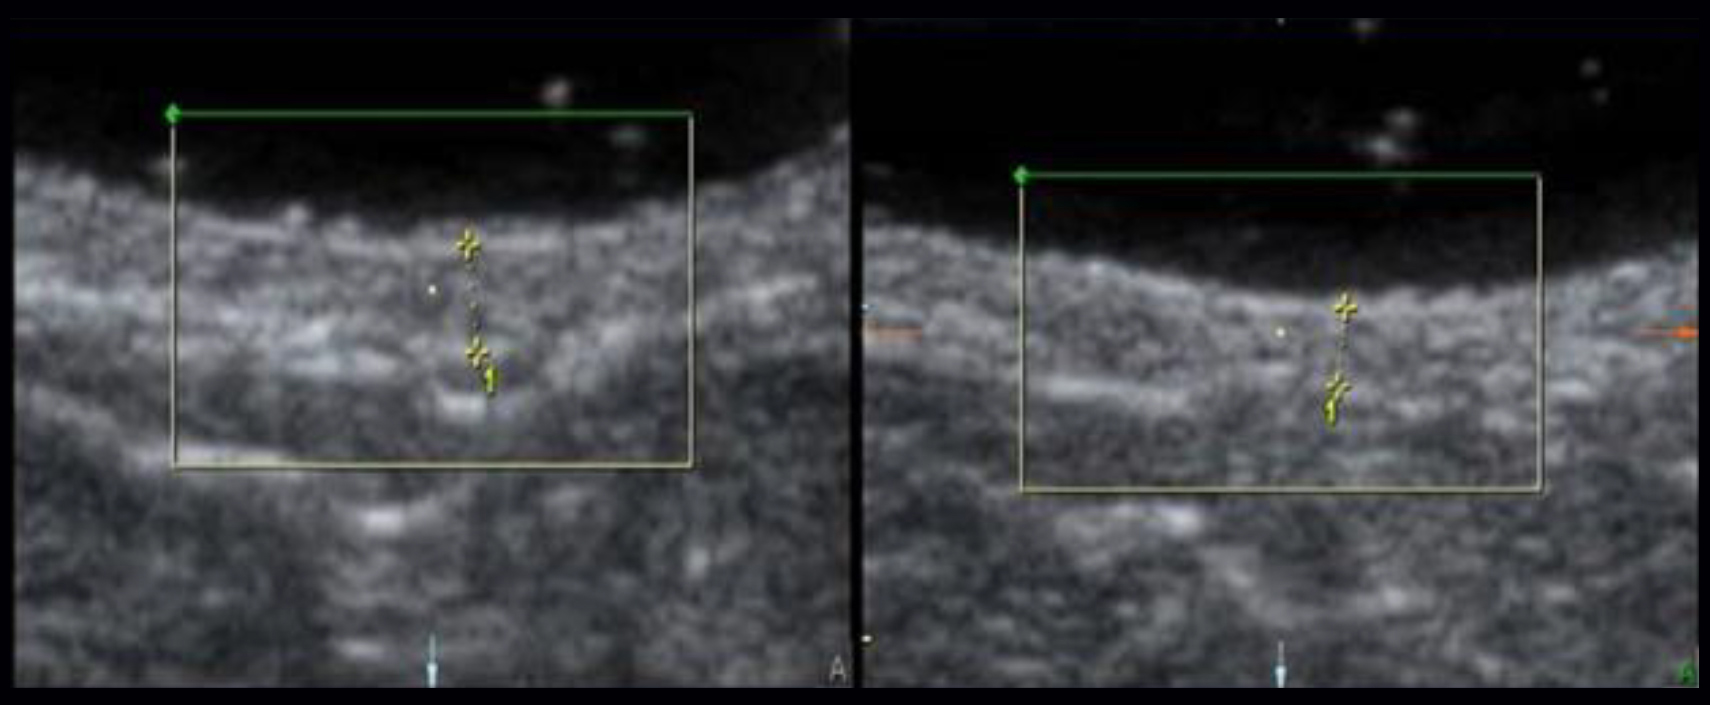

Cesarean scar release therapy (SRT) is a scar reduction technique that is simple and highly effective for reducing the negative influence of scars. Using the latest scientific advances to address both chronic pain and dermal scarring that occurs post-surgery, Microcurrent Point Stimulation penetrates deep into scar tissue to increase intercellular metabolism, reduce scar size, and relieve chronic pain throughout the body. SRT is so effective in releasing scars that it actually reduces scar size.